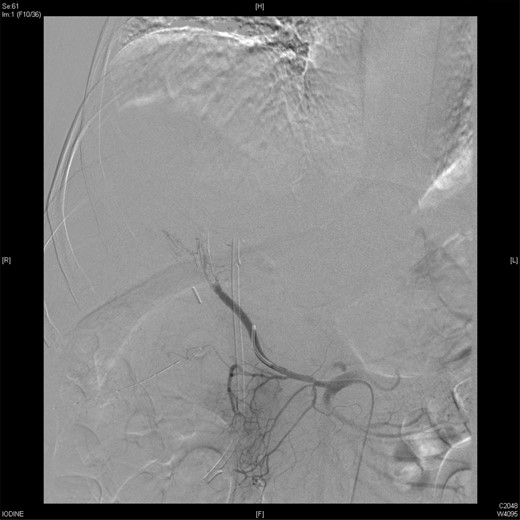

Upon presentation to our center, the patient was febrile (38.9°C) and complained of a left upper limb pain and swelling. The surgical drain was draining a mixture of bile and blood. His WBC count was 14 × 109/l, total bilirubin 35 µmol/l and the direct bilirubin 21 µmol/l. A duplex ultrasound of the upper limb revealed a left brachial vein thrombosis. Hematology was consulted, and a diagnosis of acute upper limb venous thrombosis was established. Owing to the presence of blood in the drain, he was kept on the maximum prophylactic dose of unfractionated heparin. A CT angiography of the abdomen showed two collections, one at the surgical bed near the drain, and the other was subcapsular below the left lateral lobe of the liver, as well as an aneurysm of the replaced right hepatic artery with an active bleeding blush (Fig. 1). The patient was immediately referred for an angiography, which confirmed the CT scan findings (Fig. 2). An arterial stent was inserted at the location of the aneurysm (Fig. 3), and a pigtail drain was inserted to drain any residual collection. An ERCP was also performed, which revealed a Strasberg Class D injury, and a plastic biliary stent was inserted. After the angio-stent insertion and stabilization of the patient, heparin infusion was started. Five days later he developed hematemesis and melena with a significant drop in his Hb to 2 g/l, and his total bilirubin became 183 μmol/l of which 91 μmol/l is direct. A gastroscopy was performed and showed hemobilia (bleeding from the ampulla of Vater). Subsequent angiography demonstrated a leak of contrast just above the arterial stent; hence, a further stent was placed to cover that area of the aneurysm. Similar symptoms reoccurred a week later, and a new angiography showed a new aneurysm from the left proper hepatic artery. A percutaneous thrombin injection of the aneurysm was performed as the bleeding branch was unreached via direct angiography and was filling in retrograde perfusion. During recovery a chest spiral CT was performed, which revealed the diagnosis of a bilateral segmental pulmonary embolism. Heparin infusion with low targets of partial thromboplastin time of 50–60 was started.

An angiographic scan showed stent in the replaced right hepatic artery.